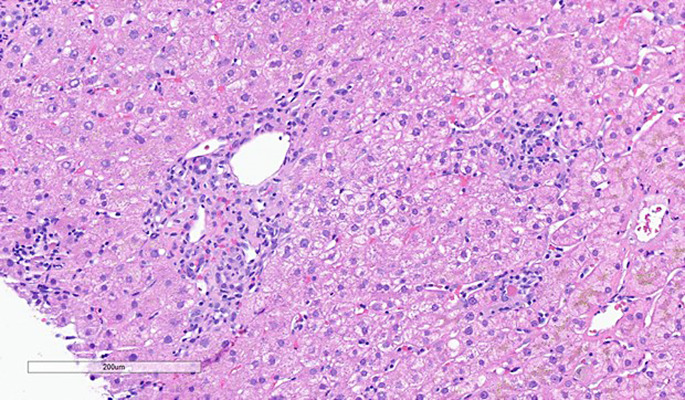

Case presentation: We present a patient with hypogammaglobulinemia, likely induced by obinutuzumab for chronic lymphocytic leukemia, found to have enterovirus meningitis and hepatitis, with elevated transaminases, headache, and relapsing fevers as primary manifestations of disease. This is the first reported case of a patient developing disseminated enterovirus infection 1 year after discontinuation of obinutuzumab course. After diagnosis, the patient was started on intravenous immune globulin therapy with improvement in symptoms and laboratory abnormalities.